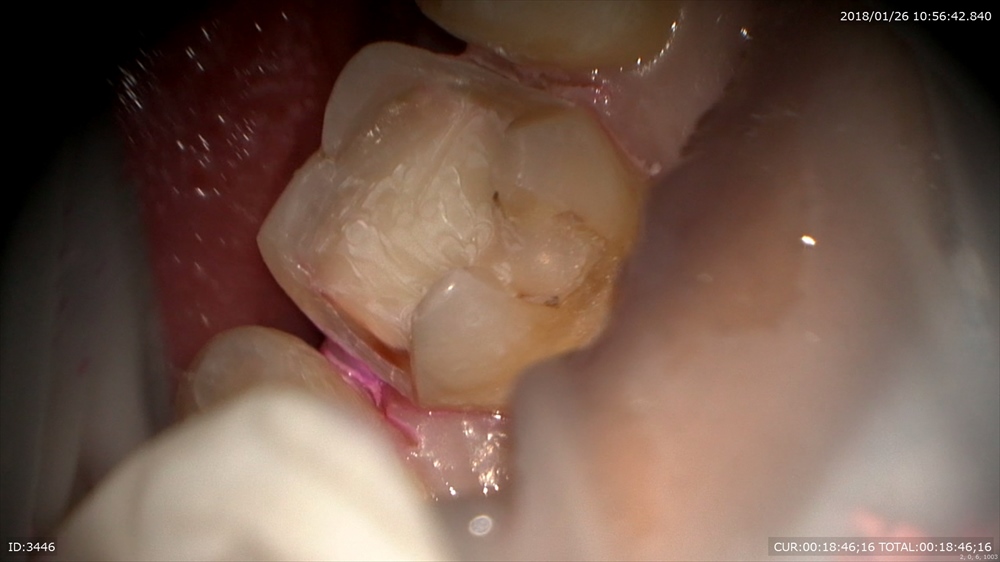

むし歯治療 穴があいていますね。

むし歯は大体中で広がります。 検知液で確認